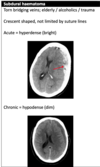

Subdural haematoma

Subdural on CT head

Left subdural with some midline shift